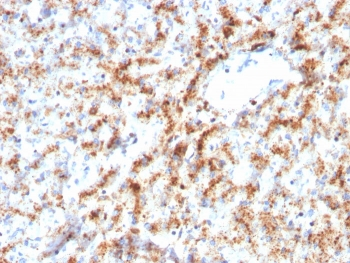

Cathepsin D Antibody

| Description | Cathepsin D Antibody |

| Tested applications | FC, ICC, IHC, IP, WB |

| Reactivity | Human, Mouse |